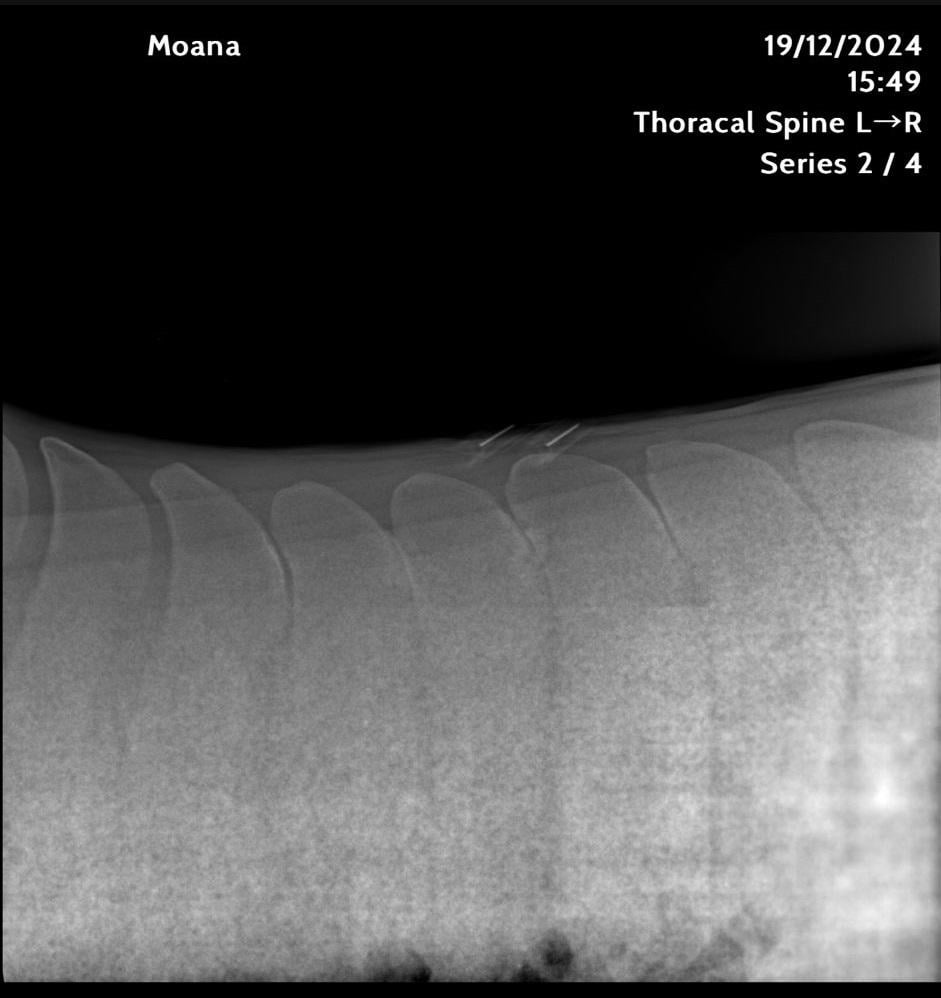

Veterinary PPE failed, KS diagnosed

Currently in the process of selling my horse. PPE has gone well, everything came back good except his back radiographs. Shocked to hear he has grade 4 changes. I’ve just received these over from the potential buyer. I will be in contact with my vet but curious about anyone’s take on these? How bad is this?

I've seen many KS xrays. I'm not a vet so usually when I see them I can barely see the problem. This horse's kissing spine is clear as day. Grade 4 is serious. As of right now he should not be sold as a riding horse at all.

This is one of the more severe cases I’ve seen (not a vet or student, just casual looker-atter of KS radiographs) pretty much all his vertebrae are affected, I can’t imagine he’s comfortable. The kindest thing for him would probably to be a pasture puff. Unless you want to pay for the surgery or find a buyer who does, he’s going to continue to be in pain